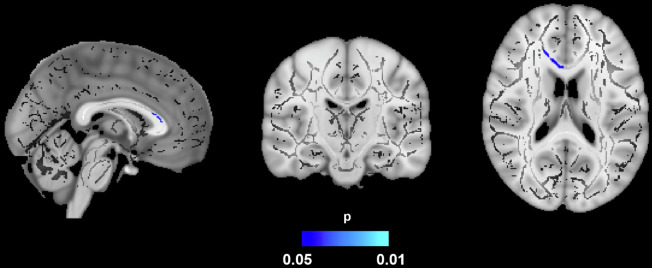

肥胖是痴呆的一个风险因素,它会造成慢性炎症状态,导致白质损伤。边缘密度成像(EDI)是一种新的技术,已经证明了量化WM变化的可靠性。30名肥胖和20名认知正常的非肥胖成年人接受了结构和扩散加权磁共振成像。内脏脂肪组织(VAT)和皮下脂肪组织(SAT)通过体素分析套件进行定量,分离脂肪组织和非脂肪组织的信号强度。扫描由管道(MaPPeRTrac)处理以生成EDI。在肥胖的参与者中,VAT/SAT比率和EDI之间存在负相关,而在非肥胖的参与者中没有看到。此外,男性的EDI比女性低。这项研究的结果表明,肥胖,通过WM损伤,可能增加痴呆的风险,性别是一个潜在的差异因素。EDI在描述肥胖和痴呆的神经病理学方面显示出了希望。

Obesity is a risk factor for dementia, creating a chronic inflammatory state that results in white matter (WM) injury. Edge density imaging (EDI) is a novel technique that has demonstrated reliability in quantifying WM changes. Thirty obese and 20 non-obese cognitively normal adults underwent structural and diffusion-weighted magnetic resonance imaging. Visceral adipose tissue (VAT) and subcutaneous adipose tissue (SAT) were quantified via VOXel Analysis Suite by separating signal intensities of adipose and non-adipose tissue. Scans were processed by a pipeline (MaPPeRTrac) to generate EDI. Among obese participants, there was a negative association between the VAT/SAT ratio and EDI, which was not seen among non-obese participants. Additionally, males had decreased EDI compared to females. The results of this study suggest that obesity, through WM damage, may confer increased risk of dementia, with sex as a potential differential factor. EDI demonstrates promise in delineating the neuropathology of obesity and dementia.